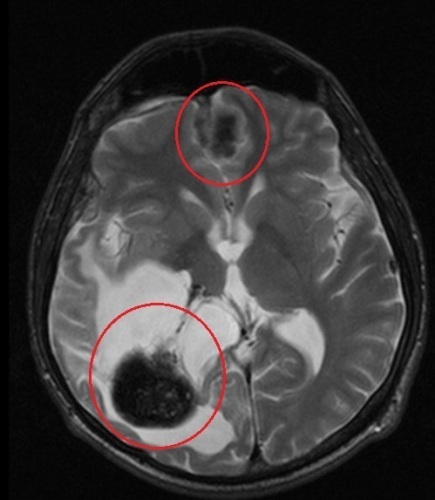

@janina9410 Tak som si to lepsie precital a zistil som, ze ta chemo sa dava pri gliome optickeho nervu. Ja mam tie nadory po celom mozgu a jeden na sluchovom nerve, takze mna sa to netyka. Ja na kozne nechodim a nikdy som ani nechodil. Z tych spominanych priznakov nemam vlastne ziadne okrem tych nadorov. Vsetky ostatne neurologicke problemy su nasledkom operacie a ozarovania, pred operáciou som bol mlady stastny chalan. Po operacii mi ochrnula lava polovica tela a trvalo velmi dlho kym som to neustalou rehabilitáciou ako-tak rozchodil. No aj tak mi zostal ochrnuty clenok, zhorsena jemna motorika, absencia periferneho videnia, zhorseny sluch. Po oziareni tretieho nadoru sa mi zacali lamat kosti a mam zosrobovany bedrovy klb. Ja som si myslel, ze je to nasledok ozarovania, no dr. povedala, ze to byva následok liekov, ktore sa po ozarovani beru. Ja som to vzdy bral tak, ze primarny nador je ten prvy a tie ostatne su matastazy. Iba predvcerom jedna lekarka poznamenala, ze tie nadory by mohli byt pricinou nejakej inej choroby a spomenila prave NF. Tu mozes vidiet dva moje najvacsie nadory a biele miesto je diera po operacii.